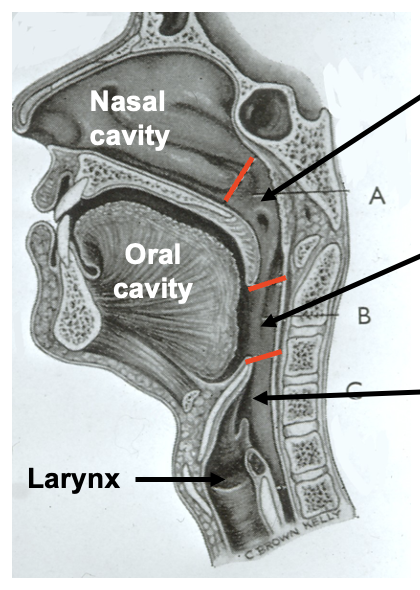

name the pharyngeal constrictor muscles

three pairs of pharyngeal constrictor muscles

superior constrictor

middle constrictor

inferior constrictor incl. cricopharyngeus (part of inferior constrictor)

function of pharyngeal constrictor muscles

sequentially constrict the pharynx to propel the bolus of food down towards the oesophagus

pharyngeal constrictor muscles: structure

pharyngeal constrictor muscles are circular but not fully closed anteriorly

posteriorly the muscles are joined at the midline via the fibrous pharyngeal raphe

name the pharyngeal longitudinal muscles

three pairs of pharyngeal longitudinal muscles

stylopharyngeus

salpingopharyngeus

palatopharyngeus

function of the pharyngeal longitudinal muscles

elevate the larynx

shorten and widen the pharynx during swallowing

which structure is the pharynx innervated by

the pharynx is innervated by the pharyngeal plexus (branches of CN IX and CN X)

where is the pharyngeal plexus located

the pharyngeal plexus of fine nerves spread under the lining (sensory innervation) and muscles (motor innervation) of the pharynx

which nerves form the pharyngeal plexus

pharyngeal branches of the glossopharyngeal nerves (CN IX)

pharyngeal branches of the vagus nerves (CN X)

branches from the external laryngeal nerve (branch of the superior laryngeal nerve which is a branch of the vagus)

sympathetic fibres from the superior cervical ganglion

pharyngeal motor innervation: which nerve innervates the pharyngeal muscles

all of the muscles of the pharynx are innervated by the vagus nerve (CN X)

pharyngeal motor innervation: which pharyngeal muscle is the exception to being innervated by the vagus nerve

the stylopharyngeus muscle (longitudinal) receives motor innervation from the glossopharyngeal nerve (CN IX)